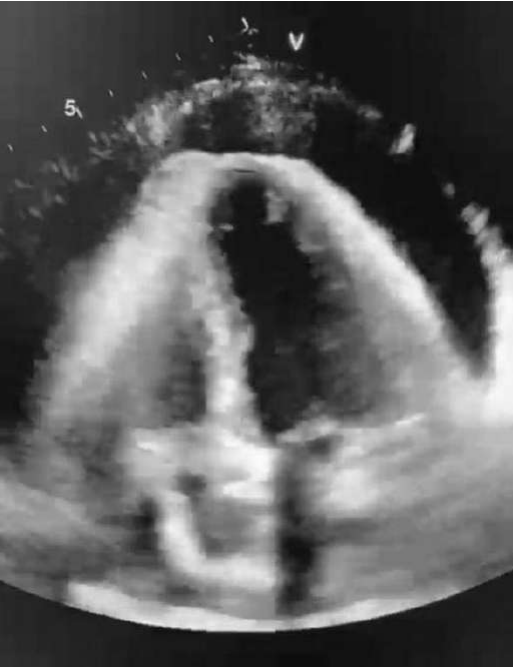

Uma paciente de 40 anos de idade chega ao pronto-socorro referindo ortopedia, edema de membros inferiores e dispneia aos pequenos esforços de início há cerca de 1 semana. Ao exame físico, apresenta-se dispneica, com extremidades frias, com palidez cutânea e com frequência cardíaca de 120 bpm; eletrocardiograma com padrão de baixa voltagem e alternância elétrica. Foi realizado ecocardiograma à beira-leito, conforme se vê na imagem abaixo.

Assinale a alternativa que indica a conduta mais adequada diante desse caso clínico.